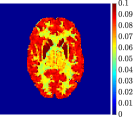

Finally, Figure 8 represents the last frame of the dynamic PET data reconstructed with the mean parametric values returned by reg-AS-TR, reg-GN, and lsqcurvefit, with respect to the noise-free, 10-noise, and 20-noise IFs.

In general, reg-AS-TR and lsqcurvefit seem to provide similar mean reconstructions, although uncertainties associated to lsqcurvefit are significantly bigger. On the other hand reg-GN seems to systematically underestimate the parameter values within region . Furthermore and as expected, for all methods the quality of the parametric reconstructions deteriorates with increasing noise levels; this is more clear from the and parametric images, probably due to the different sensitivities of the data with respect to the model parameters [37]. In reg-GN and lsqcurvefit some artifacts can be observed at the edges of the homogeneous regions, especially around region and region , whereas the effect of regularization in reg-AS-TR results in a reduced presence of artifacts while the structure of the regions is preserved. This general trend is confirmed by the error-bar plots of Figure 7. Finally, the frames in Figure 8 corresponding to reg-AS-TR show a significant improvement of the image quality with respect to what is provided by the other two approaches.